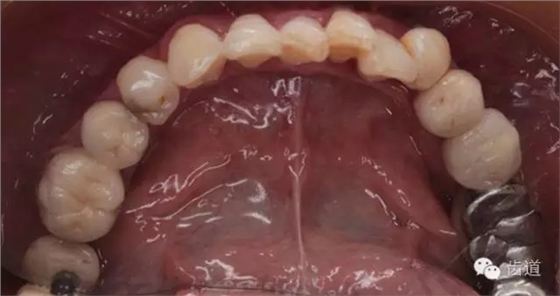

2、上頜牙合面觀

2、治療后